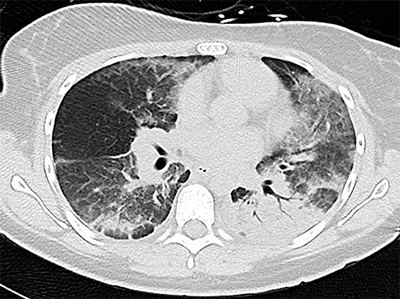

Self-reports of vaping THC directed providers to widen their differential diagnoses to include EVALI due to the connection between vaping products containing vitamin E acetate and the development of a systemic inflammatory response. Pneumonia was also considered, as well as appendicitis related to abdominal symptoms. While results from blood and urine analysis and imaging were negative, chest X-rays indicated mild opacities. The patients’ vaping history prompted a chest CT, which further revealed bilateral ground-glass opacities in all three patients leading to a diagnosis of EVALI. Treatment included methylprednisolone, ceftriaxone, and azithromycin. Patients were weaned off oxygen support and discharged home within two to three days with instructions to complete their full course of treatment and follow-up with a pediatric pulmonologist to confirm symptom resolution.

An example of a CT scan of the lung.